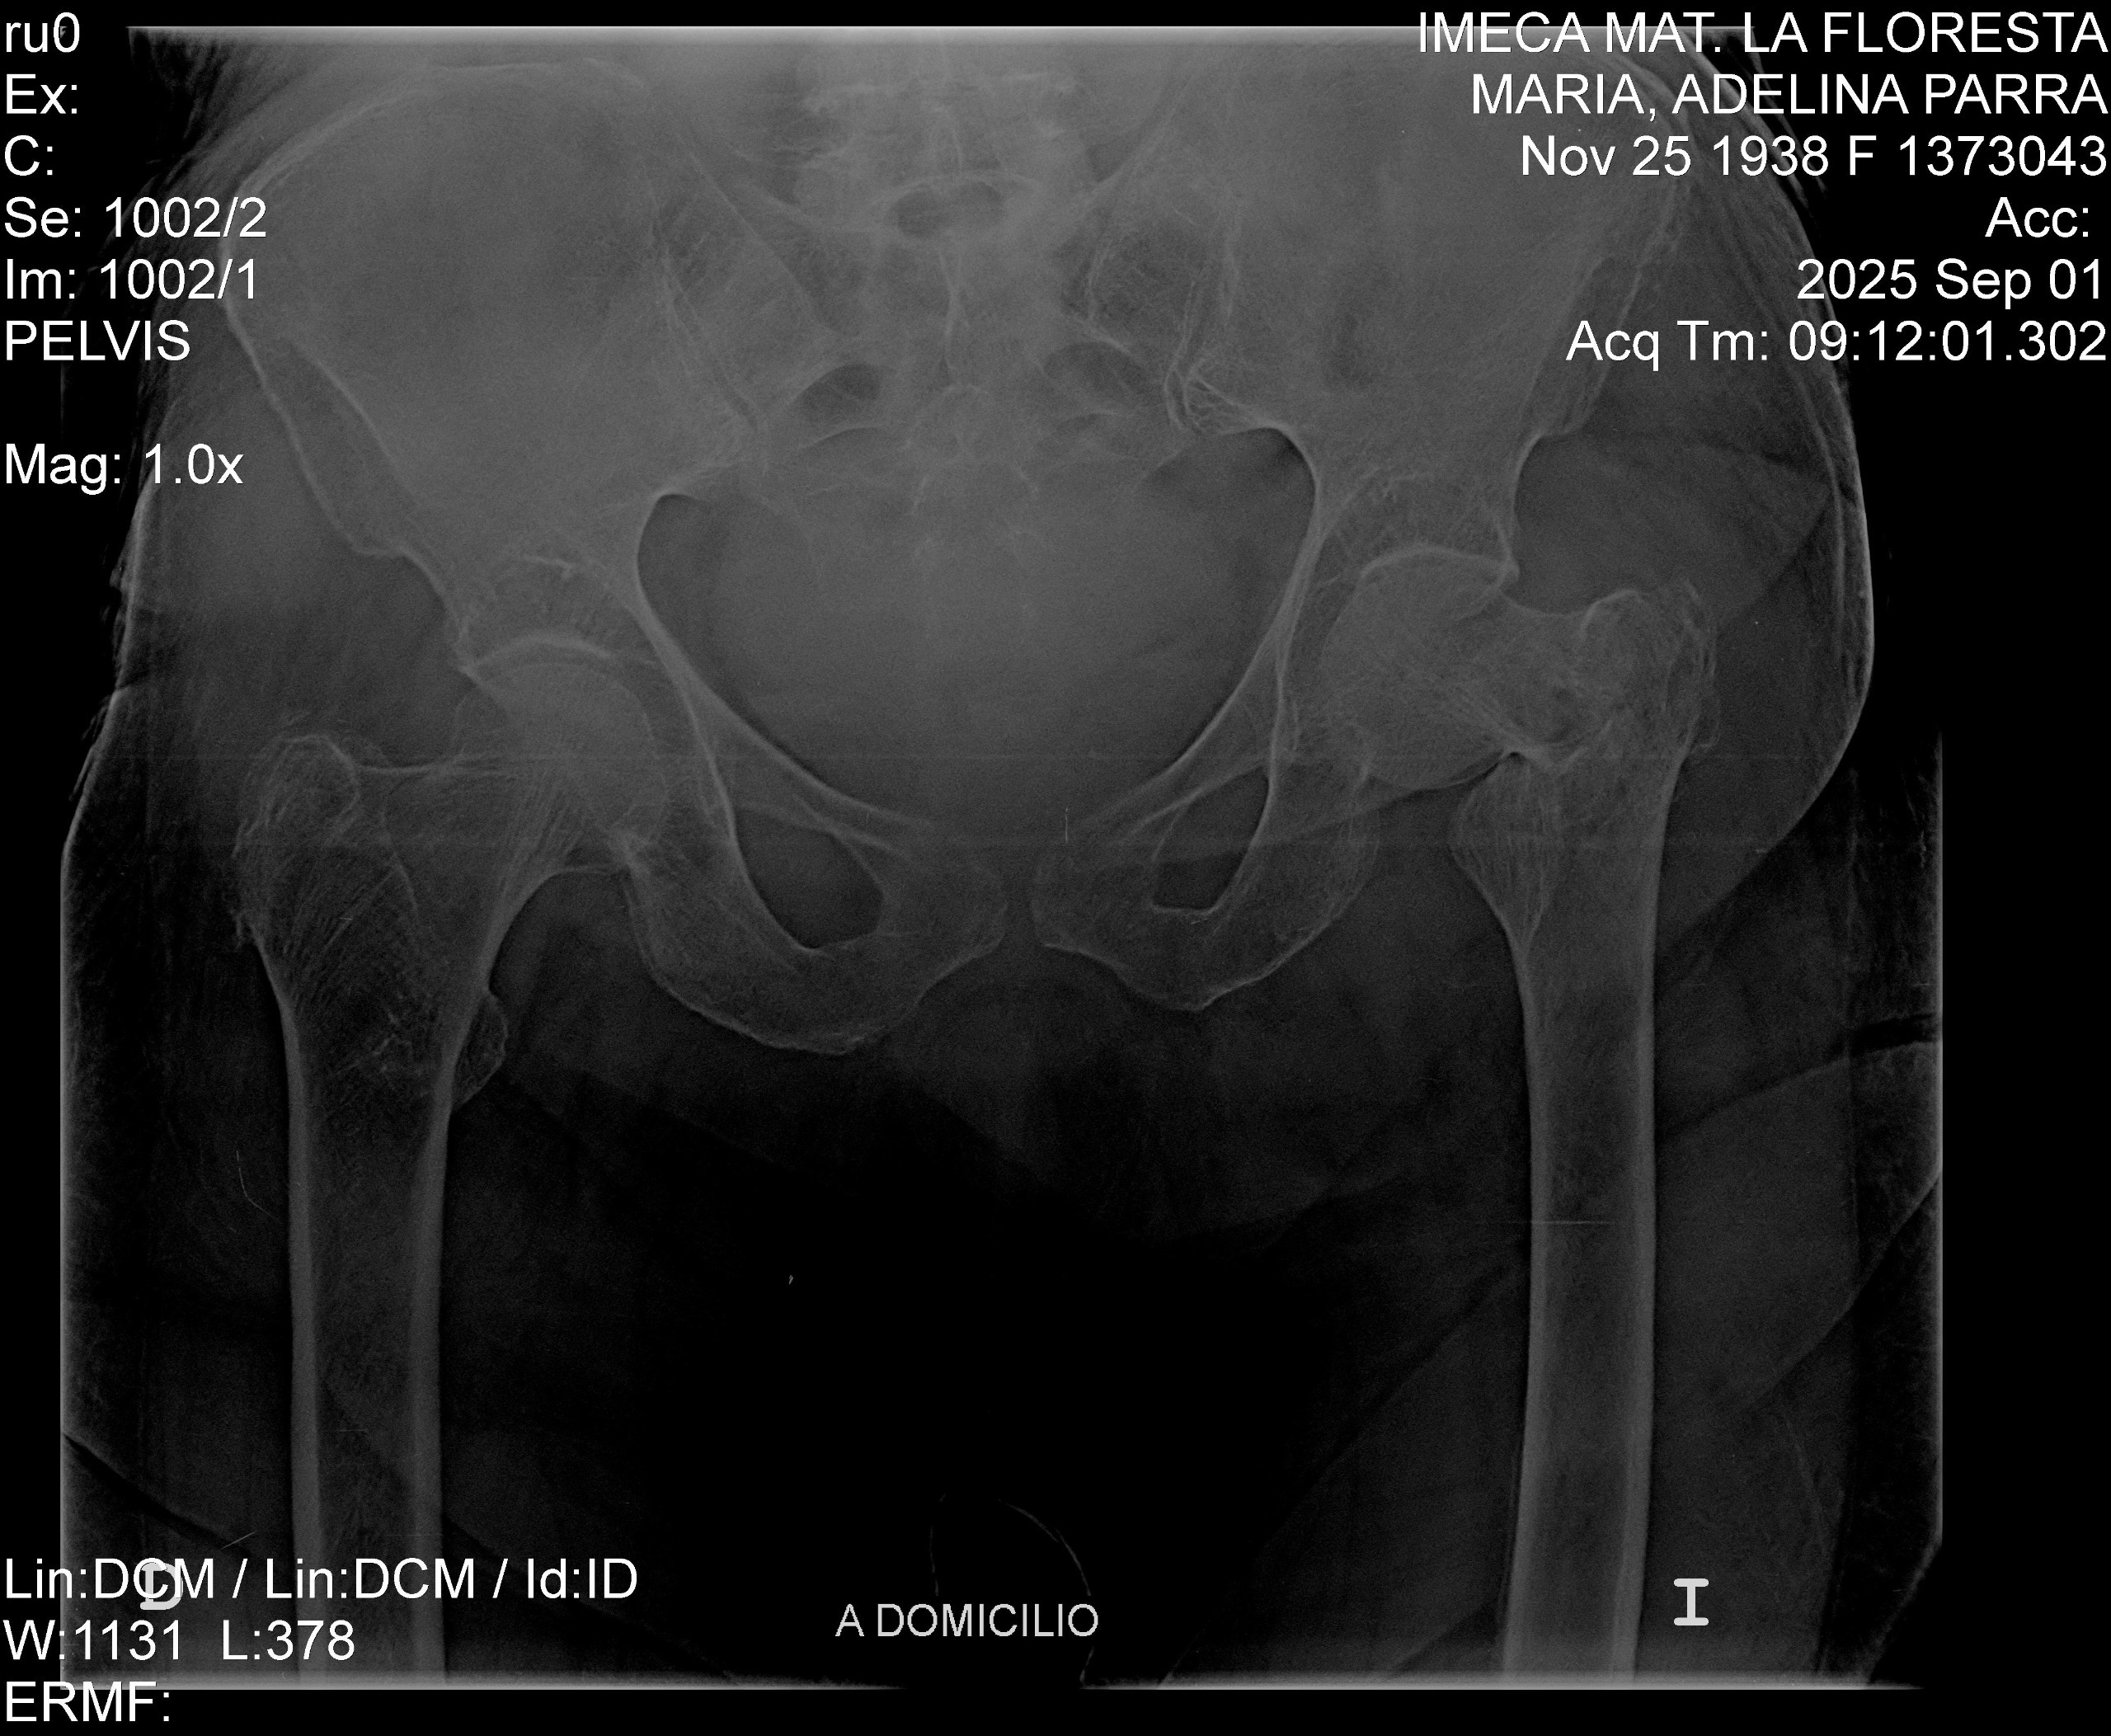

Recently, my grandmother suffered a terrible fall and fractured her left femur. She now requires extensive surgery to replace the femur, and the medical expenses are overwhelming. Our family is doing everything we can to support her, but the costs of the surgery, hospital care, and recovery are far more than we can manage alone.

Recientemente, mi abuela sufrió una fuerte caída y se fracturó el fémur izquierdo. Ahora necesita una cirugía extensa para reemplazar el hueso, y los gastos médicos son abrumadores. Aunque nuestra familia está haciendo todo lo posible para apoyarla, los costos de la cirugía, la atención hospitalaria y la recuperación superan lo que podemos manejar solos.